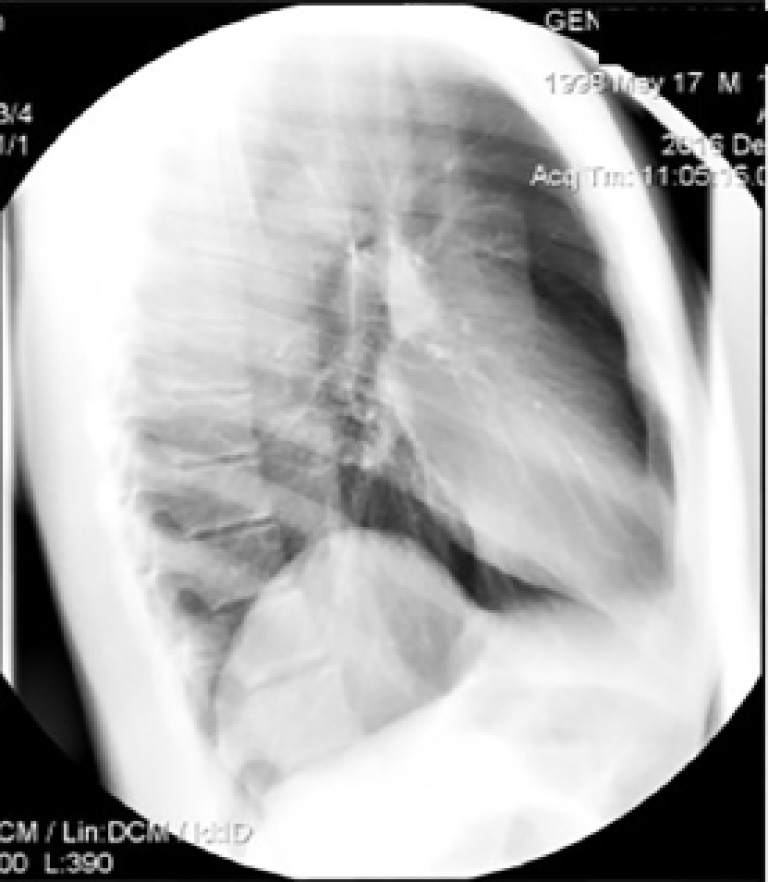

На рентгенограмме органов грудной полости в боковой проекции (рис. 2) в заднебазальных отделах правого легочного поля визуализируется округлое затемнение.

Рис. 2. Рентгенограмма органов грудной полости пациента Н. в правой боковой проекции в положении стоя